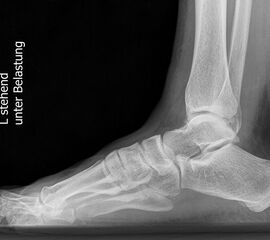

Standard ist die belastete Röntgenaufnahme des Fußes dorso-plantar und seitlich. Günstig ist eine Röhrenkippung von 10°-20°, um die Gelenke der Lisfranc-Linie einsehen zu können.

Ergänzend kann eine Schrägaufnahme hilfreich sein. Bei Metatarsalgien oder Pathologien der Sesambeine liefert die Sprinteraufnahme zusätzliche Informationen. Bei einer Pes planovalgus Fehlstellung wird ergänzend ein Saltzman view durchgeführt.

• Elevation/ Plantarisierung I. Strahl